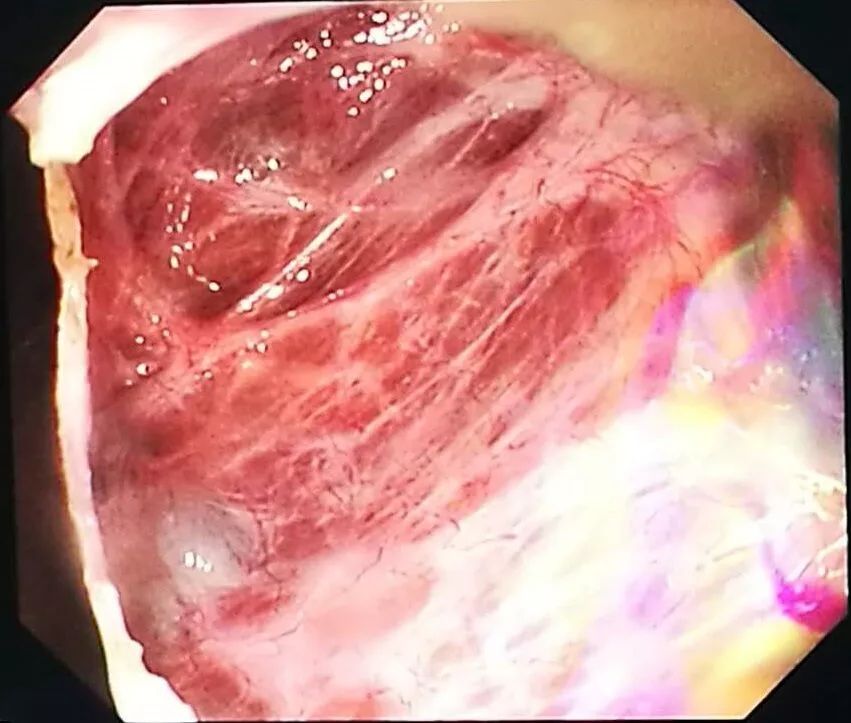

△內(nèi)鏡下切除囊腫壁

術前,經(jīng)過全面分析討論和準備后,蘇軍凱博士團隊為其經(jīng)臍NOTES內(nèi)鏡下開窗引流手術,術中證實腹腔粘連,軟式內(nèi)鏡利用其柔軟、多方向可調(diào)優(yōu)點,繞過多處腸粘連,順利切除了巨大肝囊腫的囊壁。手術過程順利,患者術后無明顯疼痛感覺,當天即可飲水,第二天恢復良好,下地活動、進食進水,隨后第三天就康復出院了。